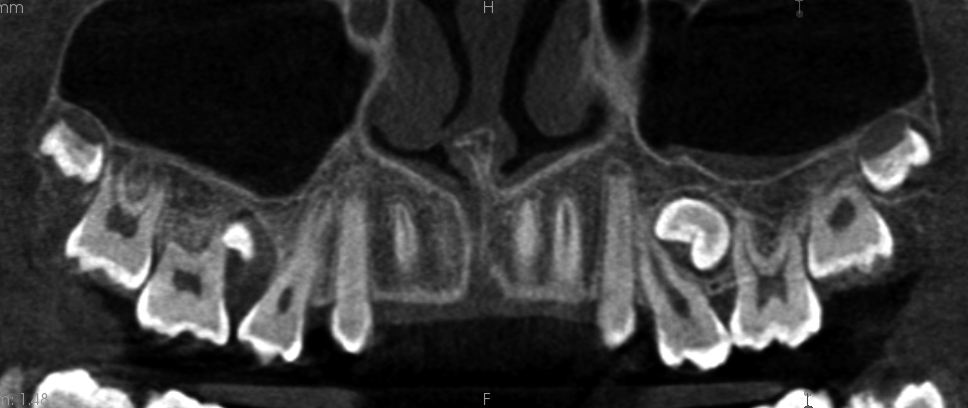

Resorpcja zęba to proces powstania ubytku twardych struktur zęba wywołanego przez osteoklasty bez kontaktu ze środowiskiem jamy ustnej, między innymi na skutek ucisku wywieranego przez ząb zatrzymany. Dla lekarza ortodonty jest istotne ustalenie, czy zęby zatrzymane lub twory nadliczbowe powodują resorpcję zębów stojących w łuku w celu wczesnej eliminacji przyczyny resorpcji. Celem pracy jest przedstawienie opisu przypadku zastosowania tomografii stożkowej w diagnostyce nieprawidłowo położonych zawiązków zębów przedtrzonowych drugich górnych. Stwierdzono, że tomografia stożkowa jest skuteczną metodą oceny wczesnej resorpcji zewnętrznej korzeni zębów.

Tooth resorption is the process of appearing of a defect of hard tissues of teeth caused by osteoclasts not having contact with oral cavity environment, eg. due to mechanical pressure exerted by an impacted tooth. It is essential for an orthodontist whether impacted teeth or supplementary teeth cause resorption of erupted teeth in order to early eliminate the causative factor of the resorption. The aim of the paper is to describe a case report of cone-beam computed tomography (CBCT) in diagnostics of incorrectly located germs of upper second premolars. It was found that CBCT was an efficient method of imaging of early external root resorption.